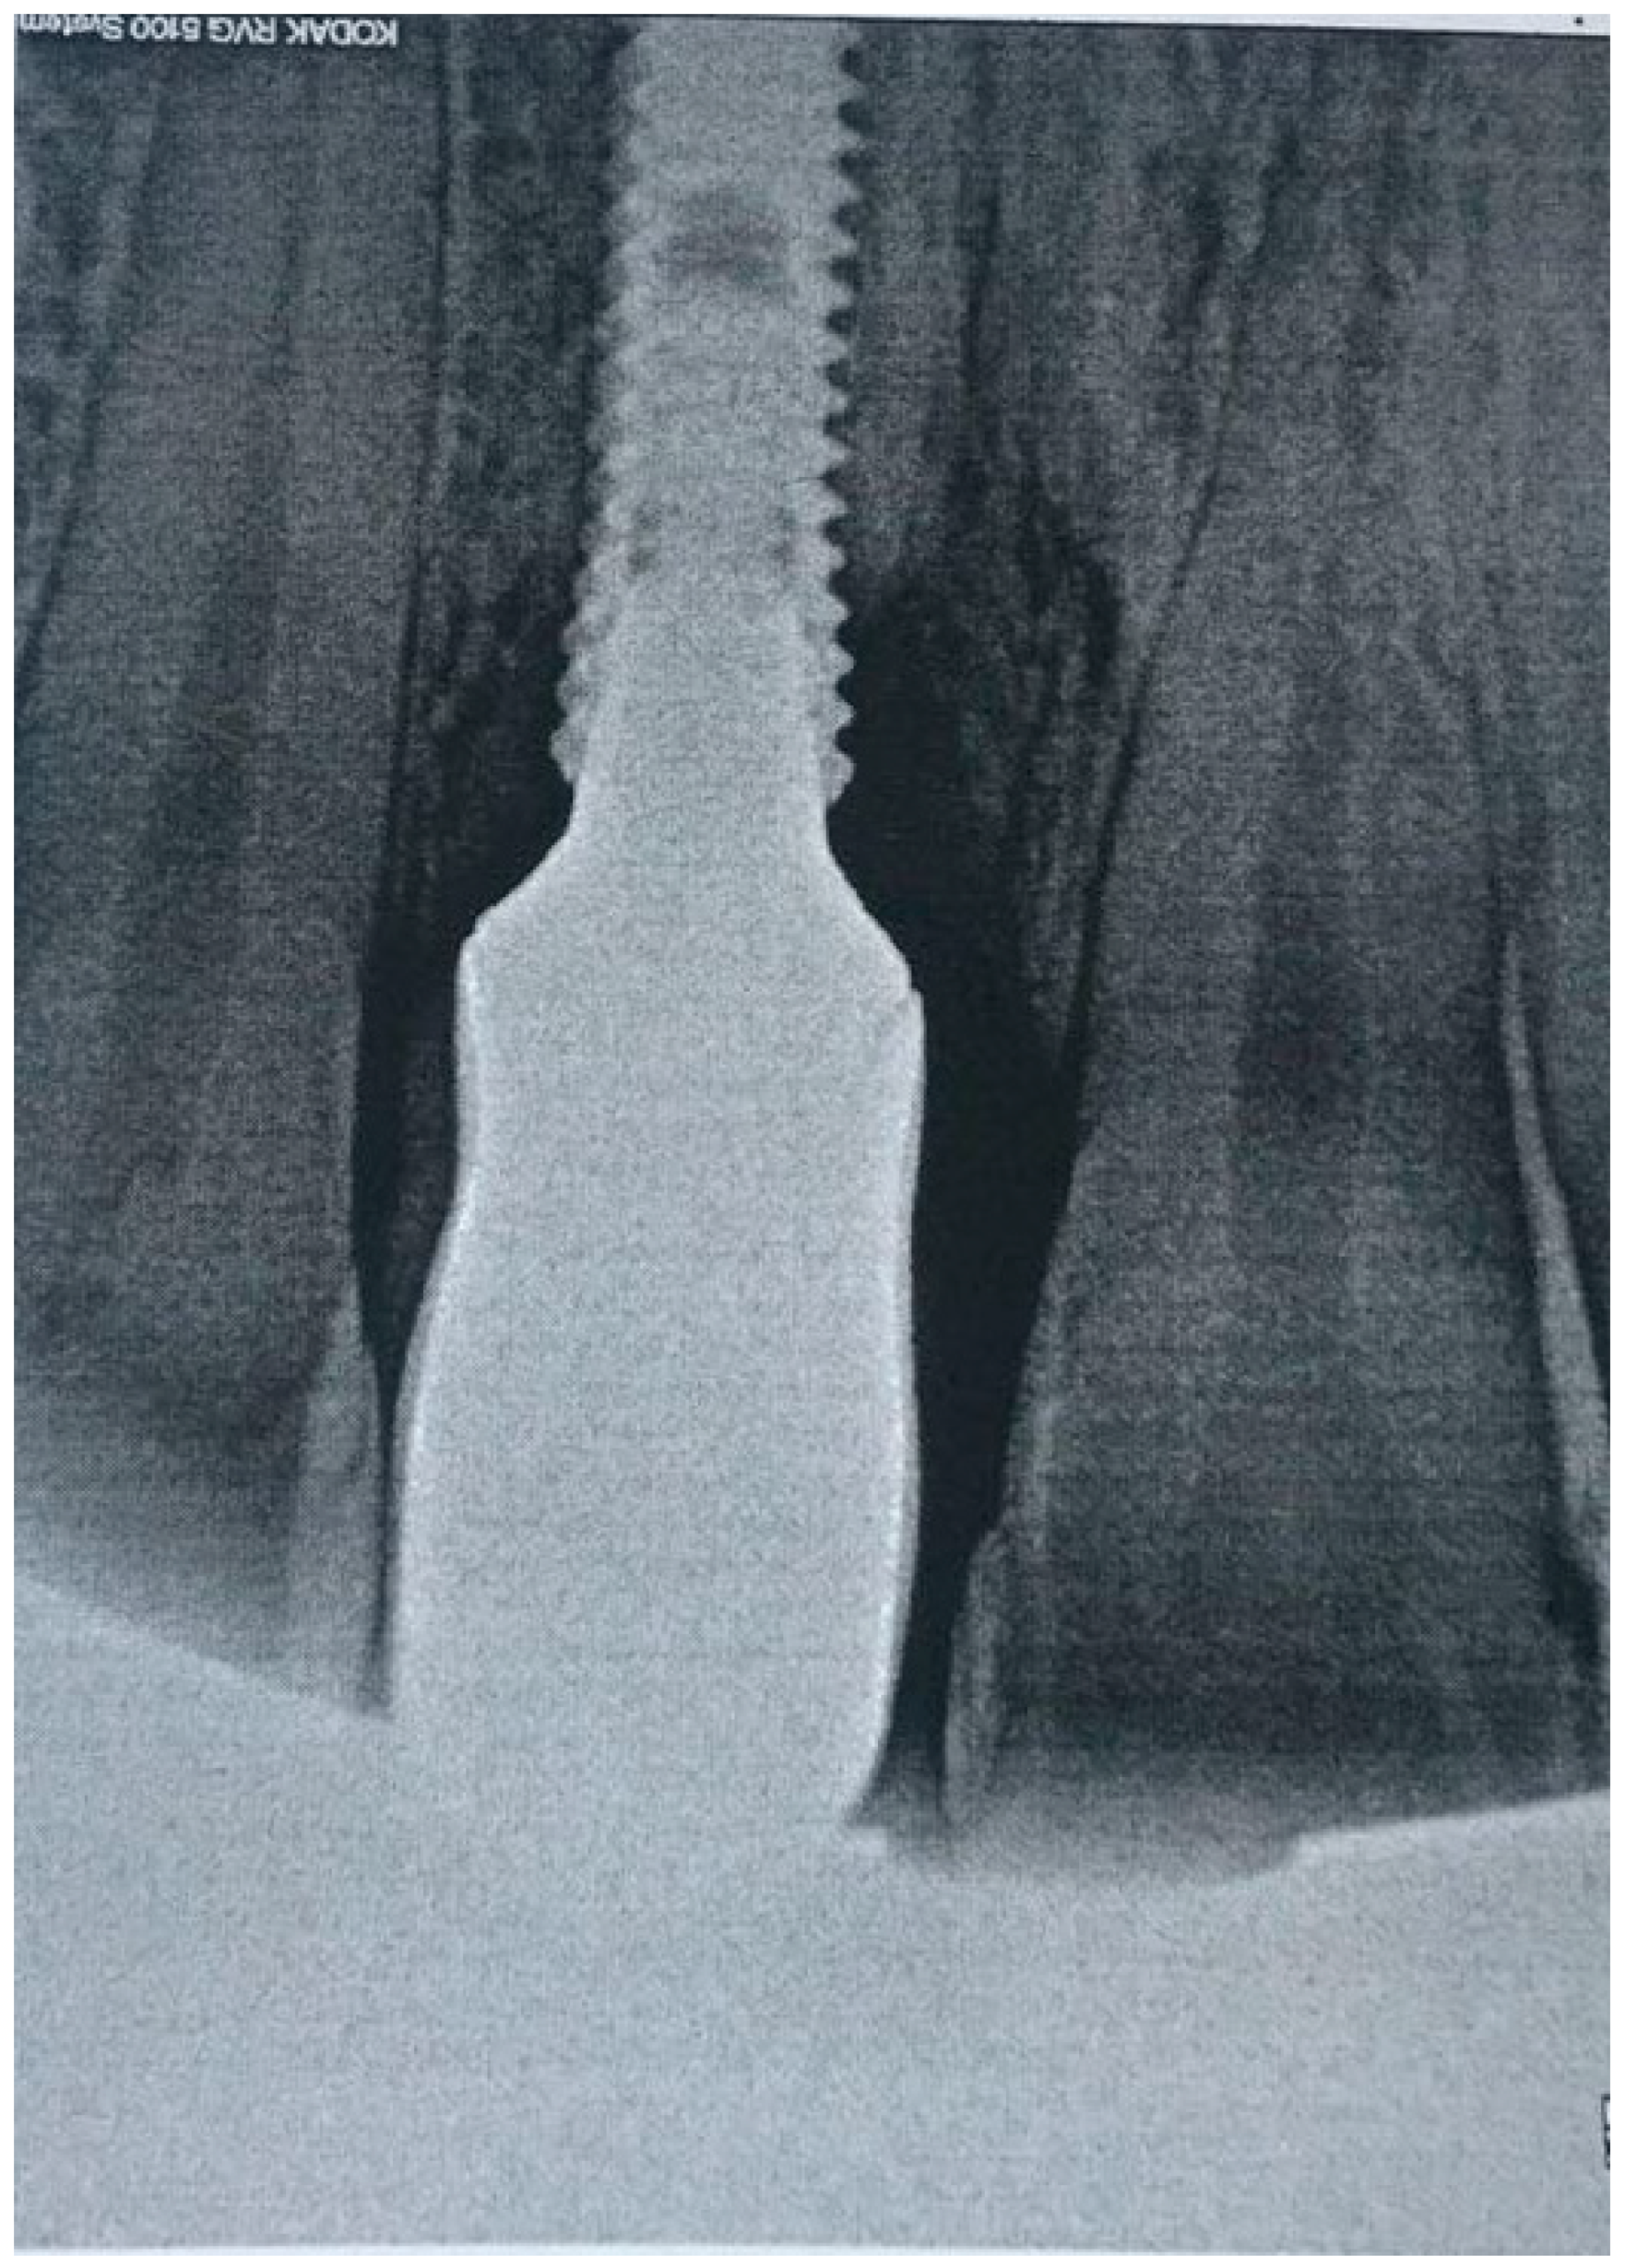

2.1. Case Report 1